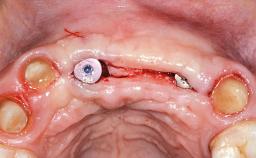

In 2001, a 48-year-old woman presented at a dental clinic with a failing fixed partial denture spanning from teeth 13 to 21. She was experiencing pain upon function, tenderness to palpation facial to tooth 13, and severe mobility of the prosthesis. Radiographic and clinical assessment revealed a subcrestal fracture of tooth 13, making its restoration unlikely. It was determined by the clinician that the tooth needed to be extracted prior to proceeding any further with dental care. After the extraction, the patient lost confidence in the progression of her treatment and sought consultation at the Center for Implant Dentistry. At her consultation visit in our clinic, an extra- and intraoral clinical examination revealed a medium lip line at full smile and an edentulous area spanning from 13 to 12 with both vertical and horizontal deficits in hard and soft tissue.

Bone Augmentation Horizontal|Staged|Vertical

Augmentation Materials Autogenous chips|Autogenous block(s)|Membrane

Soft Tissue Grafting Staged